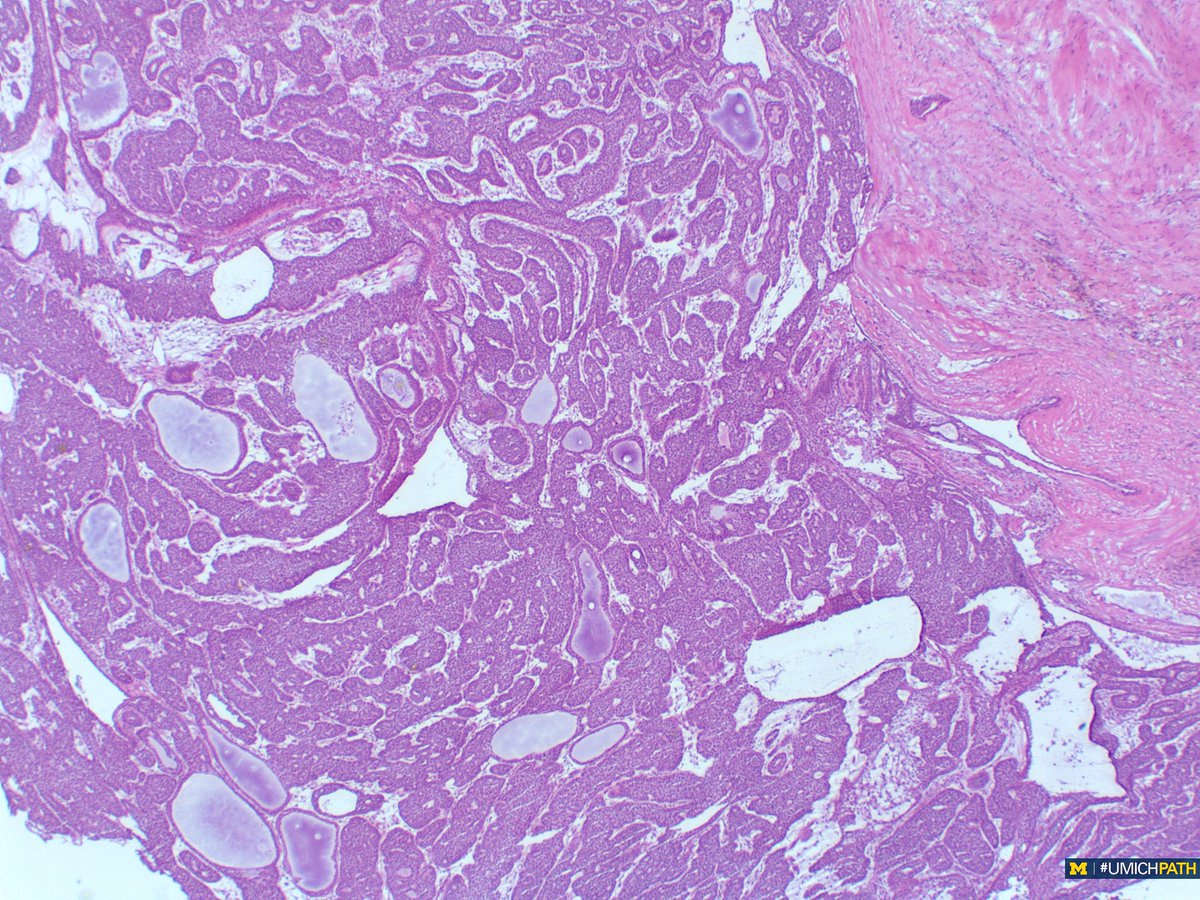

🔬: #COTW from @MeredithKHerman! Intraoperative Frozen Consult of a parotid mass from a 60yo F. What is your differential diagnosis? #UMichPath #Pathology